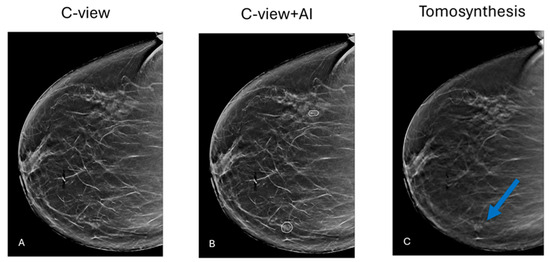

Early Results of Using AI in Mammography Screening for Breast Cancer

Background: Recent advancements in Artificial Intelligence (AI) have the potential to address the challenges of mammographic screening programs by enhancing the performance of Computer-Aided Detection (CAD) systems, improving detection accuracy, and reducing false positive rates and recall rates. These systems were mostly [...] Read more.

Background: Recent advancements in Artificial Intelligence (AI) have the potential to address the challenges of mammographic screening programs by enhancing the performance of Computer-Aided Detection (CAD) systems, improving detection accuracy, and reducing false positive rates and recall rates. These systems were mostly investigated by control trials using cancer-enriched datasets and multiple readers. Objectives: This study aims to evaluate the real-world impact of AI integration on the performance of a breast cancer screening program. Methods: In January 2021, our mammography unit integrated an AI system (iCAD version 2.0) into its mammographic screening protocol. This study evaluates audit data of 31,176 mammograms interpreted between 2017 and 2021, comparing 24,373 mammograms prior to AI implementation and 6803 after the integration. Logistic regression analysis was used to assess the statistical significance of changes in key screening metrics, with a significance level of p < 0.05. Results: This study assesses the impact of artificial intelligence (AI) on mammographic screening. The cancer detection rate increased significantly from 6.2 per 1000 in 2019 to 9.3 per 1000 in 2021, with cancers detected on mammograms rising to 98%. Stage 1 cancer detection reached 100%, and the false negative rate dropped to 0%. Additionally, ductal carcinoma in situ (DCIS) detection decreased from 36.4% in 2019 to 20% in 2021. These findings highlight AI’s effectiveness in improving cancer detection accuracy and efficiency. Conclusions: The integration of AI into mammographic screening demonstrated promising results in improving cancer detection rates and reducing false negative rates. These findings highlight AI’s potential to enhance screening efficacy. Full article